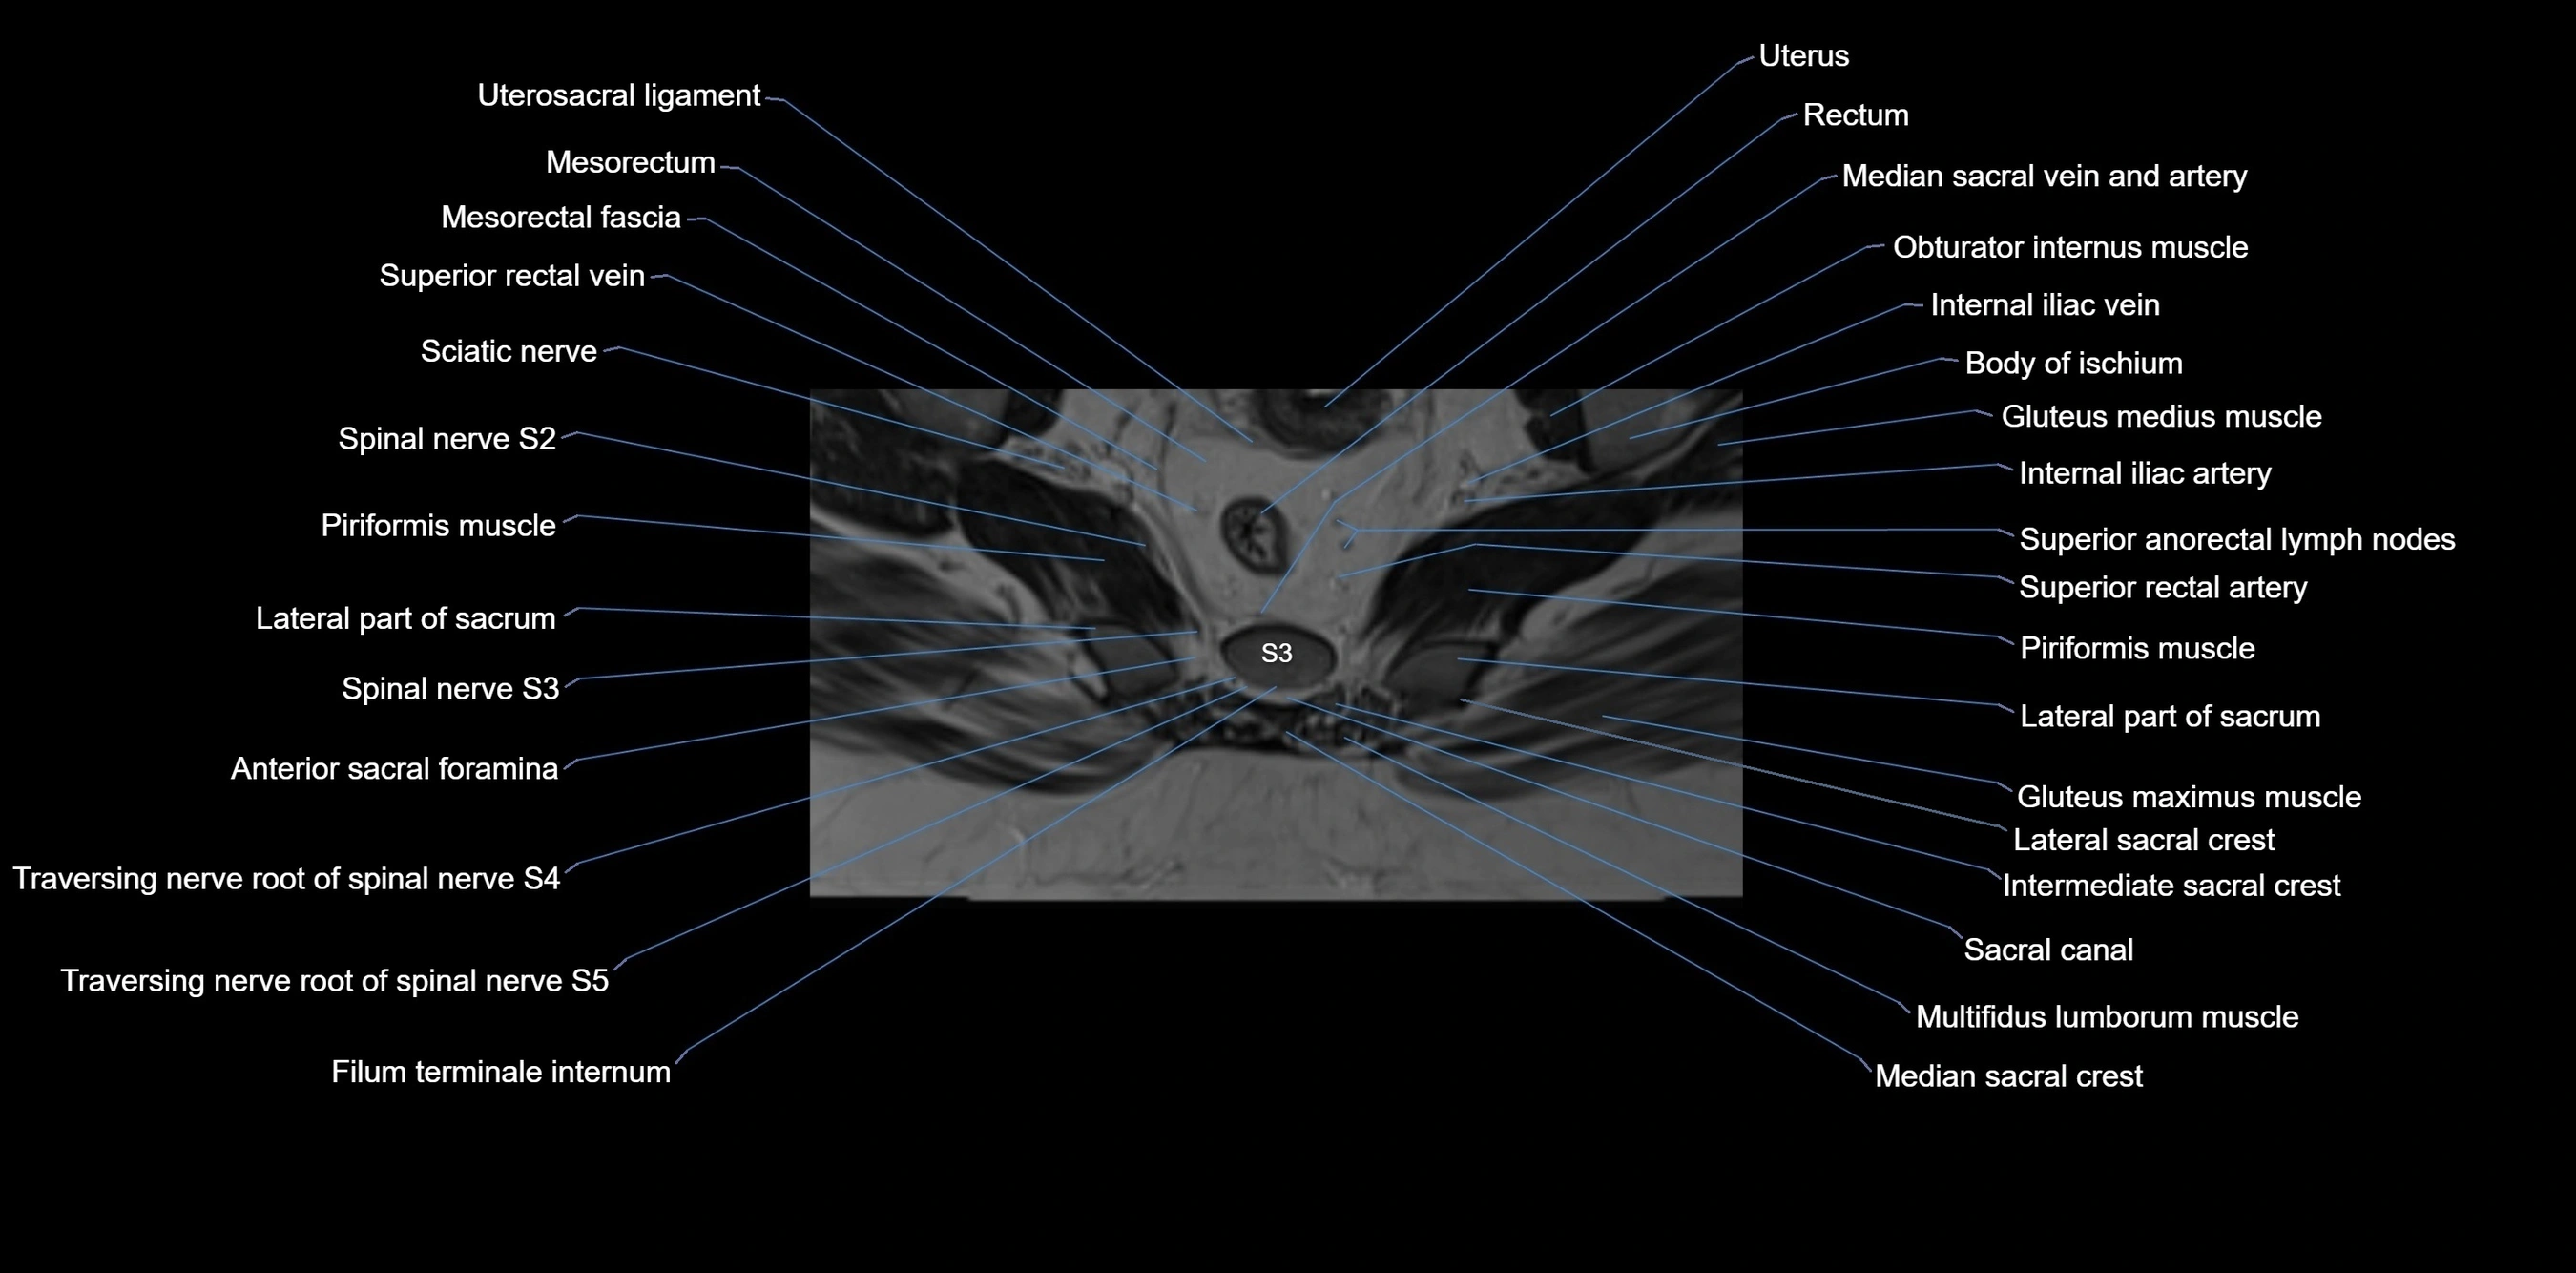

MRI image

image